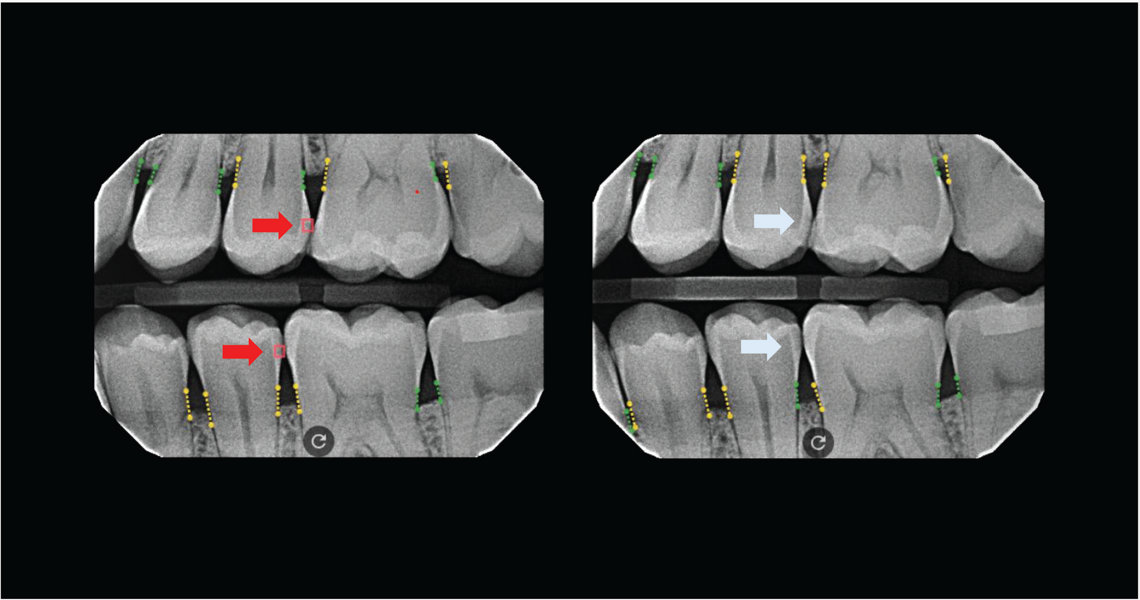

Dr. Haley Abivardi: Curodont Repair Fluoride Plus addresses a common issue that affects 80% of patients in the dental chair: early caries, often found on interproximal sites or as white spots after orthodontic treatment. As dental professionals, we refer to these as “watch areas” because, until now, there has been no effective solution. Leaving patients untreated can lead to caries progression and an increased risk of severe secondary disease.

Dr. Goly Abivardi: What makes Curodont Repair Fluoride Plus unique is its ability to treat these watch areas with a noninvasive solution during the same appointment. In just 5 minutes, this painless treatment provides a quick, effective and comfortable solution with no staining or unpleasant taste—making it suitable for all patients. By addressing early caries proactively, we can ensure better outcomes and a more positive dental experience.

Dr. Haley Abivardi: It is very encouraging to see the before-and-after cases shared by dental professionals and to have the support of the academic world, including ongoing collaborations with leading dental schools. This solution supports dental professionals in transforming their approach by addressing the subclinical signs of caries with a nonsurgical medical treatment.

Curodont offers a noninvasive and easy-to-apply solution that enhances patient care and outcomes. More than 200,000 teeth have been treated with this product in the U.S. over the past two years, enabling early intervention for watch areas that were previously left untreated.